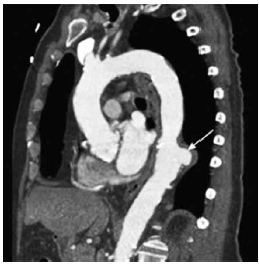

Homem, 60 anos, hipertenso, apresenta dor em dorso de forte intensidade e início súbito. FC: 90 bpm. PA: 200x120 mmHg. Realizou-se a tomografia computadorizada de aorta a seguir.

Com base no que revela o exame, a hipótese diagnóstica é: